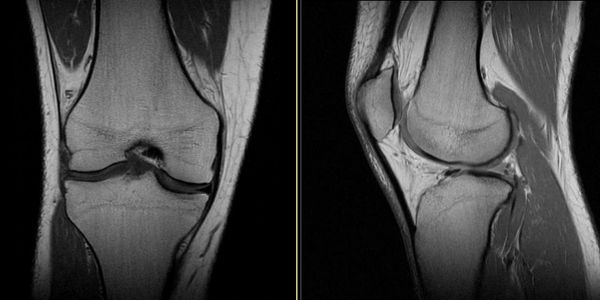

Mr Jawad Sultan is a Consultant Trauma and Orthopaedic Surgeon who specialises exclusively in knee surgery in Manchester. His clinical practice includes partial and total knee replacement, ACL reconstruction, and the management of complex multi-ligament knee injuries.

He has a specialist interest in robotic-assisted knee replacement (MAKO) and patient-specific customised knee replacement (Conformis) for selected patients. Mr Sultan treats the full range of knee conditions including knee arthritis, sports injuries, meniscal tears, patellar instability, and complex knee instability problems. His practice includes both routine and advanced knee surgery, including revision ACL reconstruction, osteotomies around the knee, cartilage restoration procedures and knee ligament reconstruction surgery.